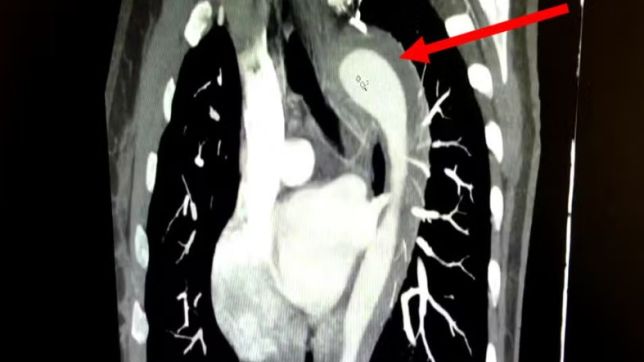

A mulher foi medicada e passou por exames que indicaram um hematoma intramural na aorta.

O hematoma intramural na aorta é uma condição grave que envolve o sangramento na parede da aorta. O quadro é considerado uma Síndrome Aórtica Aguda (SAA) e, se não tratado adequadamente, pode evoluir para aneurisma ou ruptura aórtica total, com risco de vida ao paciente.